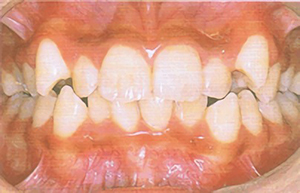

type01

• 歯の列がでこぼこしていると感じる

• 歯に食べカスが残りやすい

• 笑うと犬歯(八重歯)が見える

「叢生(そうせい)/乱杭歯、八重歯」である可能性があります。顎の大きさと歯の大きさのバランスが悪いために、歯がでこぼこに生えたり、重なっている状態です。歯が磨きにくく、そのため虫歯や歯肉炎を起こしやすくなります。歯周病にまで発展すると、若くても歯を失う可能性があります。